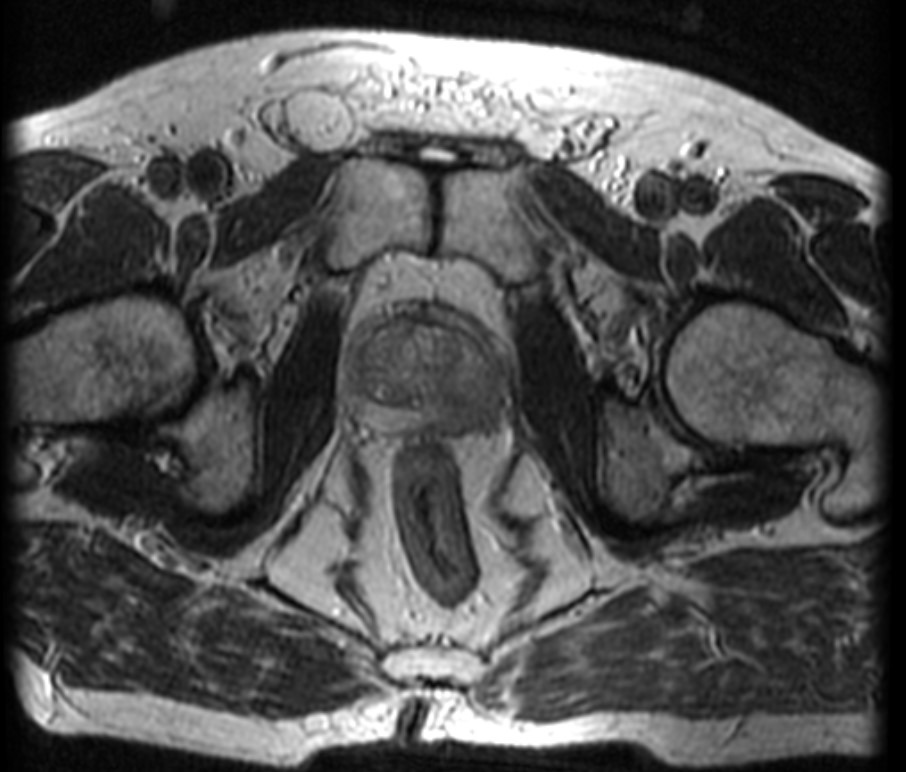

Рис. 1. МРТ (Т2-взвешенные изображения) картина поражения левой доли предстательной железы.

Стадирование при стандартном подходе подразумевает остеосцинтиграфию и МРТ органов малого таза. Магнитно-резонансная томография нужна, чтобы выявить степень локального распространения процесса в зоне простаты (прорастание в семенные пузырьки, выход новообразования за капсулу железы), а также определить, есть ли поражение регионарных лимфоузлов.